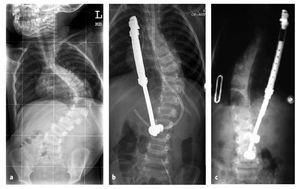

La indicación para la intervención fue en 16 casos una escoliosis congénita (figs. 24a-24c), en once casos una escoliosis neurológica y en doce casos una EIP. Las curvas se determinaron según Cobb. El ángulo de Cobb antes de la intervención medía un promedio de 65º (45-130º), y después de la intervención, un promedio de 32º (25-75º). En 18 pacientes tratamos una escoliosis torácica, en 18 pacientes una toracolumbar y en tres pacientes una lumbar (mielomeningocele). En 18 casos se utilizó un implante «costilla a costilla», en cinco casos un sistema de barra doble hasta la pelvis y en 18 casos un sistema híbrido (figs. 25 y 26).

Figuras 24a a 24c. a) Radiografía anteroposterior preoperatoria de una escoliosis congénita grave con sinostosis costales, hemivértebras, barra vertebral no segmentada y vértebra en mariposa. b) Radiografía lateral preoperatoria. c) TC tridimensional con reconstrucción. En los casos de deformidades graves puede resultar útil para la planificación de la intervención un modelo confeccionado a partir de estos datos.

Figuras 25a a 25c. a) Radiografía preoperatoria en proyección anteroposterior de una EIP con un ángulo de Cobb de 86º. b) Radiografía postoperatoria de una instrumentación «costilla a CL» realizada en una escoliosis toracolumbar progresiva. c) Radiografía postoperatoria en proyección anteroposterior después de 5 años. La curva se mantiene flexible y con buena corrección.

Figuras 26a y 26b. a) Radiografía postoperatoria en proyección anteroposterior después de corregir una escoliosis congénita mediante la técnica híbrida. b) Radiografía lateral postoperatoria.